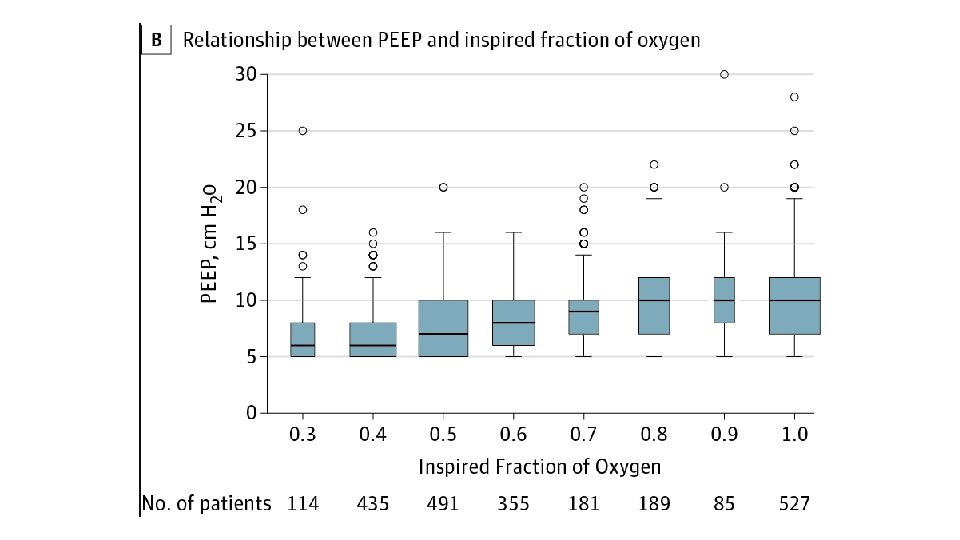

Oxygenation • Sp. O 2 > 92%; Pa. O 2 > 60 mm. Hg (regular patients) • Sp. O 2 88 -92%; Pa. O 2 50 -75 mm. Hg (ARDS and other repiratory pathology, e. g. COPD) • Aim to keep Fi. O 2 < 60%, if possible, to minimise O 2 toxicity • Use higher Fi. O 2, if necessary, but Pa. O 2 > 80 mm. Hg is excessive • If Fi. O 2 requirements rise then generally PEEP should be adjusted as well

• PEEP • • • Improves oxygenation PEEP determines FRC, aids redistribution of extravascular lung water Minimum setting is generally 5 cm. H 2 O PEEP of 10 cm. H 2 O is considered ‘moderate’ level of support Haemodynamic instability generally precludes escalation above 18 cm. H 2 O • Right heart struggles with reduced preload and increased afterload • Also impedes cerebral venous return • Approximately 25% or patients with ARDS are unresponsive to PEEP • PEEP (in general) should be titrated to Fi. O 2